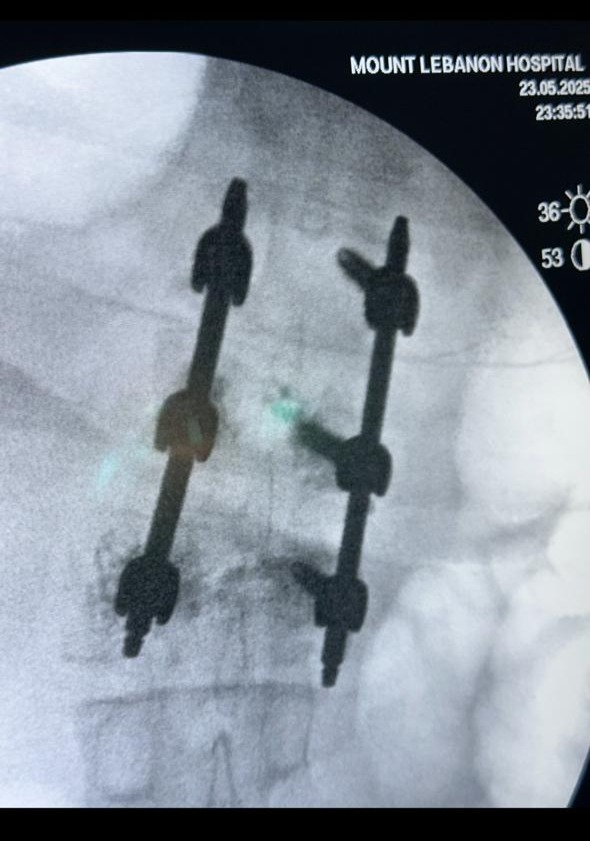

Percutaneous Screws Surgery

Percutaneous Screws Placement

Performed for spinal fractures using minimally invasive techniques to ensure stabilization, reduced postoperative pain, and faster recovery.